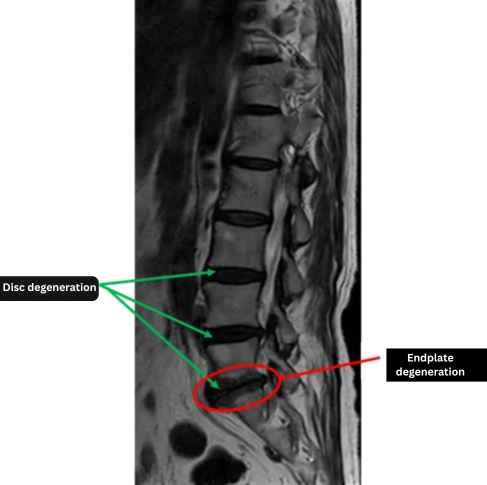

Imaging and findings

L1/2: Normal

L2/3: Normal

L3/4: Disc degeneration, lumbar instability

L4/5: Disc degeneration, lumbar instability

L5/S: Disc degeneration, endplate degeneration

The above findings were also observed on the imaging.

Significant disc degeneration, instability, and endplate changes at L3/4, L4/5, and L5/S are likely responsible for the patient’s symptoms.